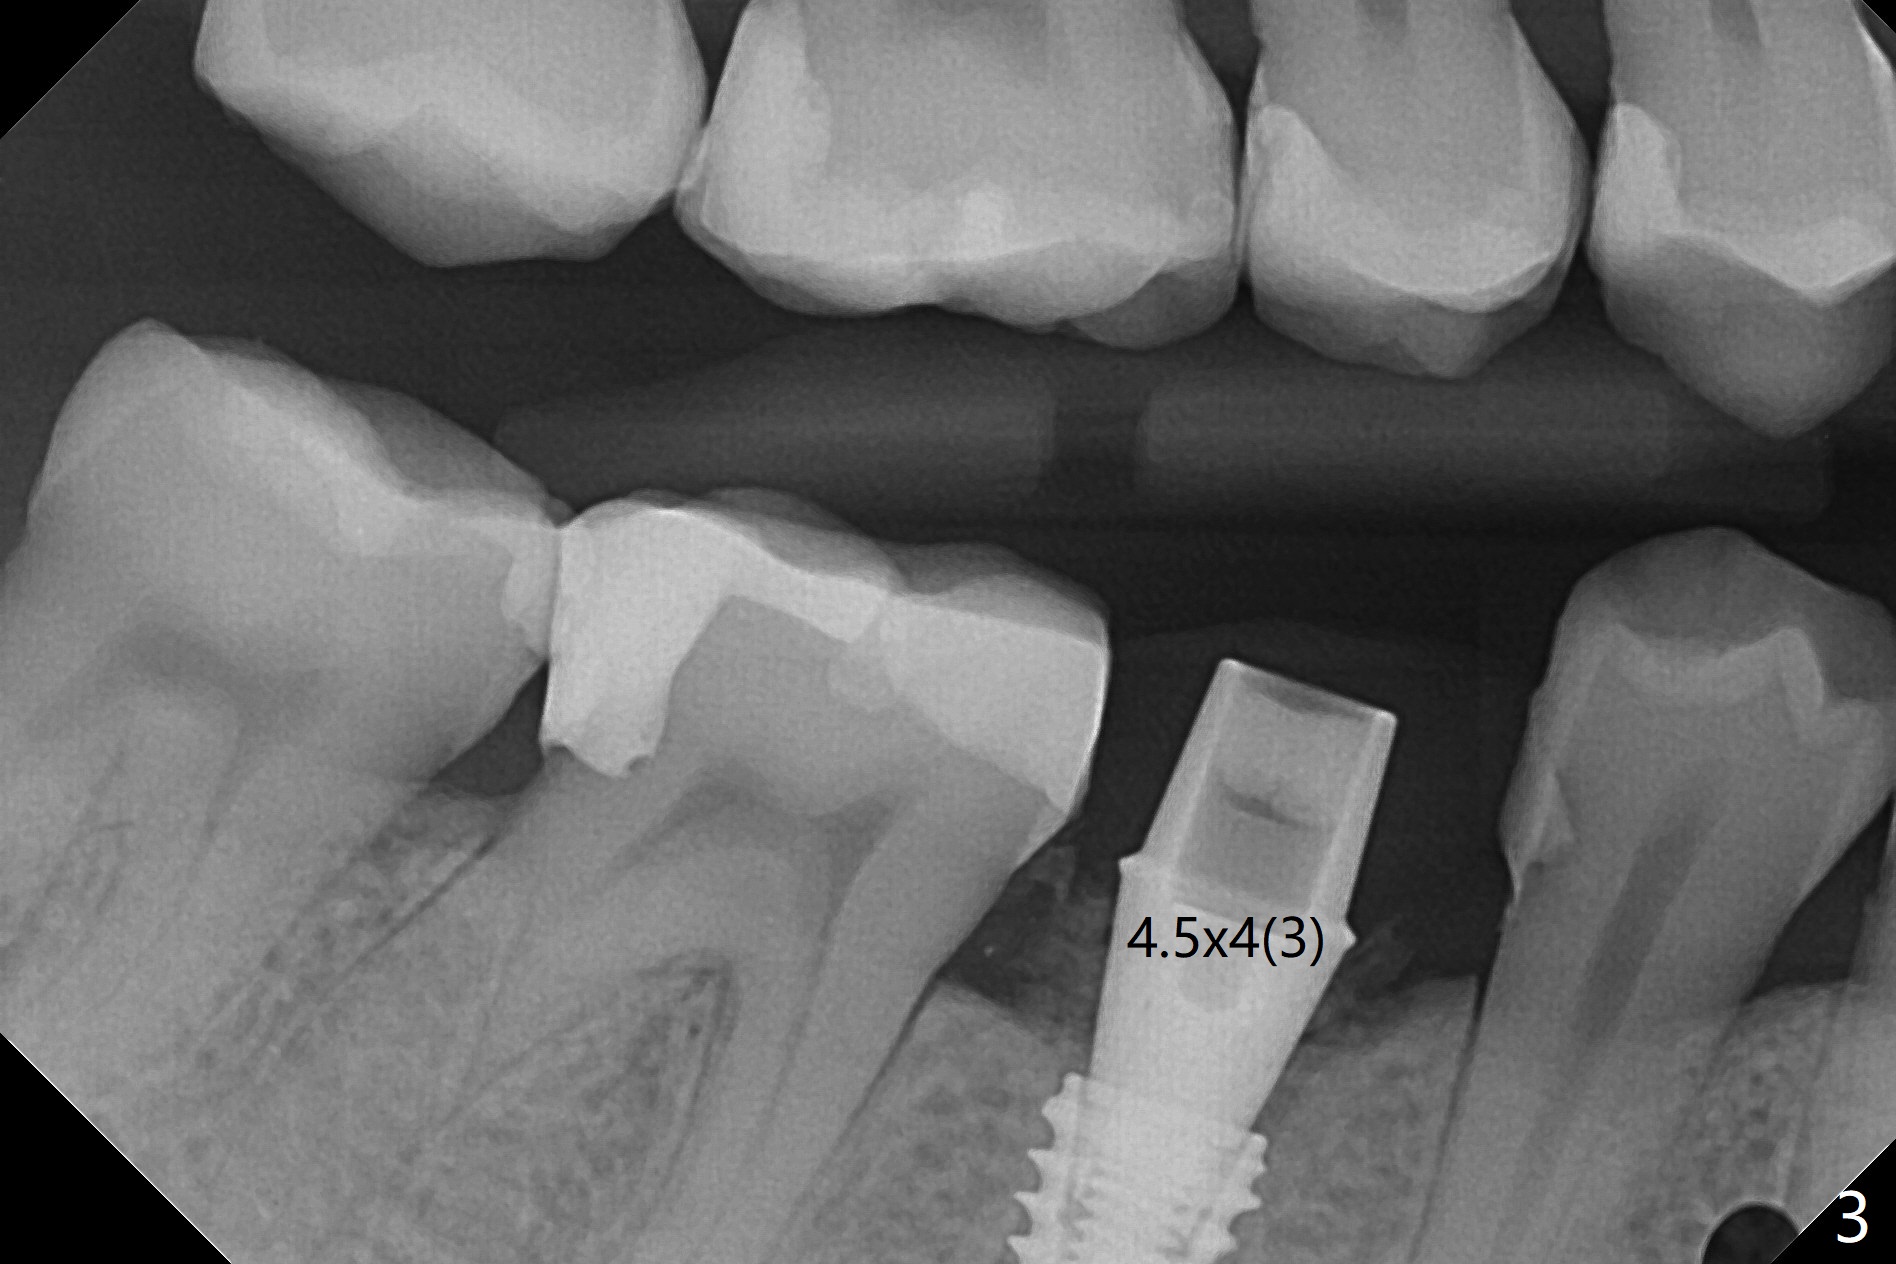

Osteotomy starts in the lingual slope of the socket of #29 with Point/Lindamann bur, but a little too distal. Gradually the osteotomy is moved mesial; the trajectory and position (Fig.1) are better than designed, but the osteotomy is close to the Mental Loop (red dashed line). When a 4x11.5 mm implant is placed, it appears to overlap the buccally positioned Loop (Fig.2 red dashed line). In fact there is no postop paresthesia. The implant placement level seems to be ideal (Fig.3 after bone graft). There is foul smell from the immediate provisional; in fact it may be due to the loose contact between the implant and abutment (Fig.4 < (4 months postop)). The gingiva is unhealthy. A 5.5x5 mm healing abutment is placed. When the patient returns 5 months postop, the gingiva is healthy after removal of the healing abutment. A 4.5x4(4) mm cemented abutment is seated without interference and torqued to 35 Ncm (Fig.5).